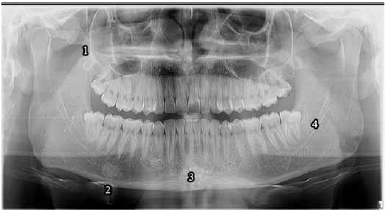

Julgue o item seguinte, a respeito dos pontos anatômicos assinalados pelos números de 1 a 4 na radiografia panorâmica apresentada.

O número 1 assinala o local em que se insere o músculo responsável pela elevação e retrusão da mandíbula.